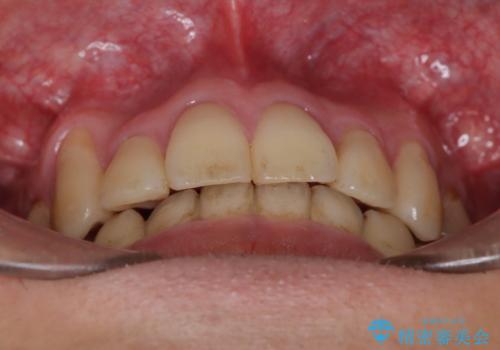

ガタガタの歯並び、八重歯をなおしたい、骨格性下顎前突 カモフラージュ矯正

- 前歯のガタガタと八重歯を治したいということで矯正を希望された患者様です。

骨格的に上顎骨が小さいために相対的に下顎骨が前に出ていたため、歯の傾きなど理想的な仕上がりが難しく、外科矯正ではなく歯列矯正の場合はカモフラージュ矯正になること説明の上、矯正治療を進めることになりました。

上顎は左右5番抜歯、下顎は左右4番抜歯しています。

途中までは下顎は全体にワイヤーをはらずに、セクショナルワイヤーにて治療を進めています。

上顎は最初から全体にワイヤーをはっていましたが、上顎前歯部の歯肉退縮のリスクが高そうだったために、途中まで下顎と同じくセクショナルワイヤーで進めています。

八重歯(3番)などは歯肉移植も検討できればよいかなと思います。